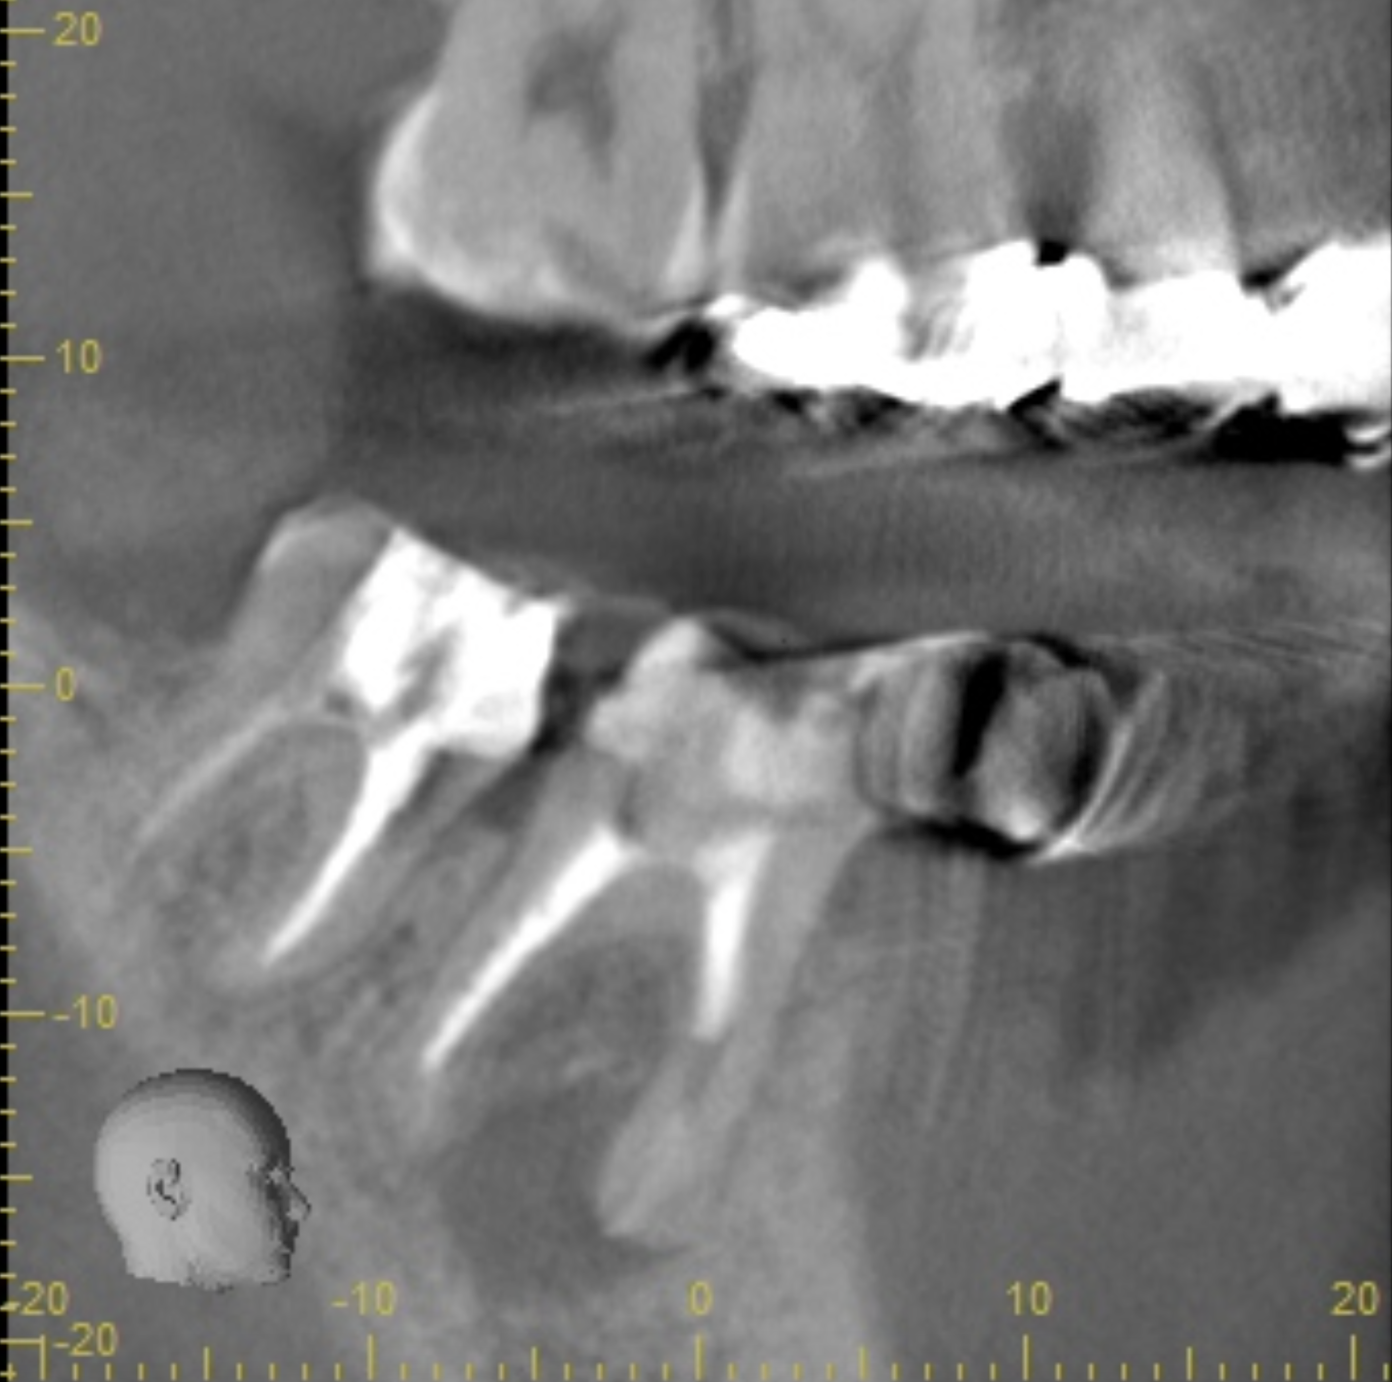

①失活による根管治療を行った

②術前CTによる根尖部の未治療および根尖透過像

| 診断 | 右下6.7根尖性歯周炎 | ||||

| 処置内容 (または主訴) | マイクロスコープ治療を用いた感染根管治療 | ||||